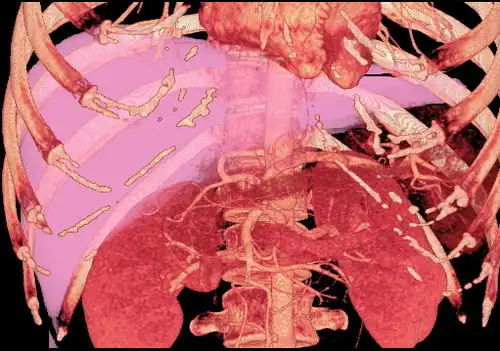

Volume rendering image created with computed tomography, which can be used to evaluate the volume of the liver of a potential donor

Living donor liver transplantation (LDLT) has emerged in recent decades as a critical surgical option for patients with end stage liver disease, such as cirrhosis and/or hepatocellular carcinoma often attributable to one or more of the following: long-term alcohol use disorder, long-term untreated hepatitis C infection, long-term untreated hepatitis B infection. The concept of LDLT is based on (1) the remarkable regenerative capacities of the human liver and (2) the widespread shortage of cadaveric livers for patients awaiting transplant. In LDLT, a piece of healthy liver is surgically removed from a living person and transplanted into a recipient, immediately after the recipient's diseased liver has been entirely removed.